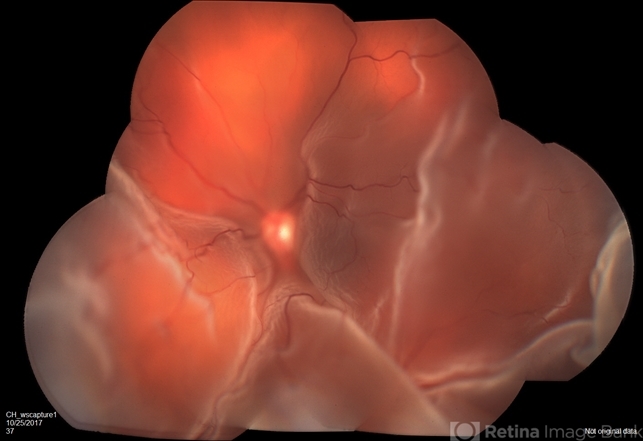

- bullous retinal detachment

- Fundus camera